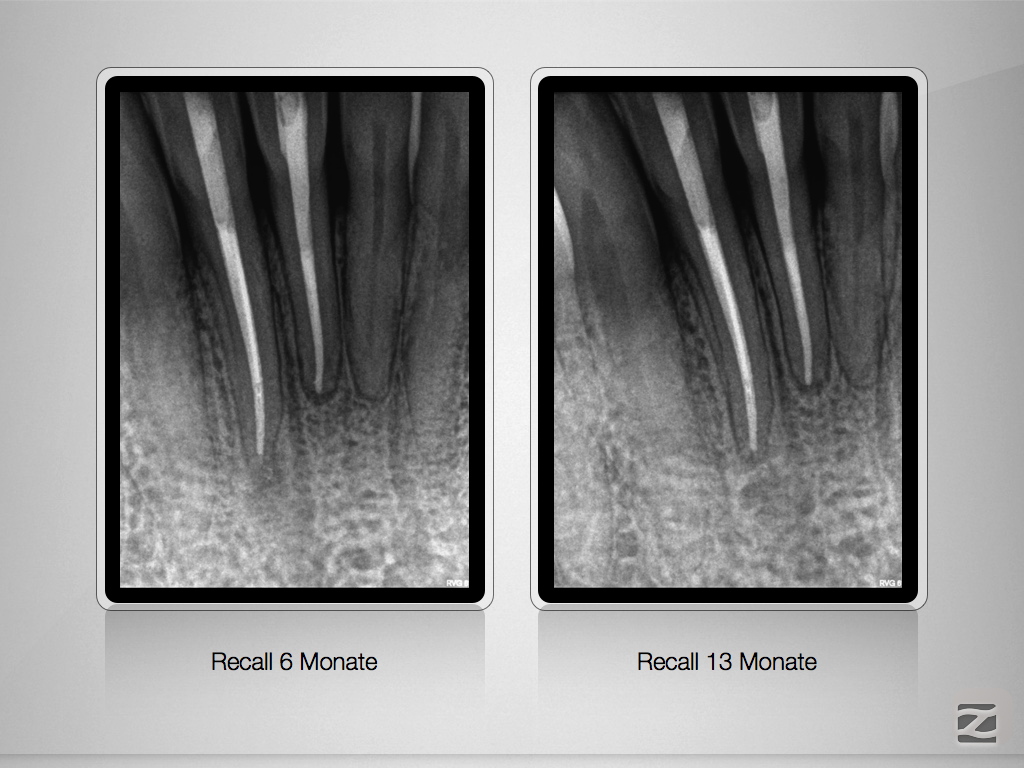

Ja ist denn schon Weihnachten?